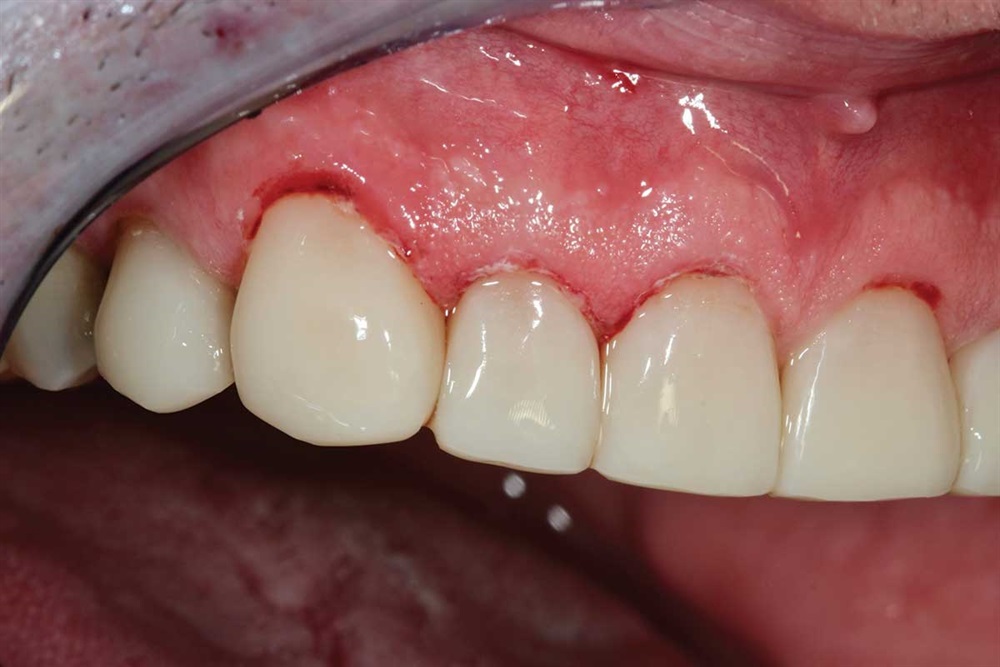

Fig. 27: Starting the maxillary teeth with 90N, rubber dam and Premier Cure-Thru contoured matrix band. Incisal view.

Fig. 28: My first increment is Z250 to provide palatal support, and then I cover that with Renamel A1.5.

Fig. 29: I cut an increment off the end of my Renamel syringe, flatten it between my finger and thumb and place on the labial of the tooth. I apply a little bonding resin on the composite increment to reduce pull-back, then work it into the interproximal and cover the tooth. Takes some time, because it does not flow like Z250.

Fig. 30: Incisal of same as above.